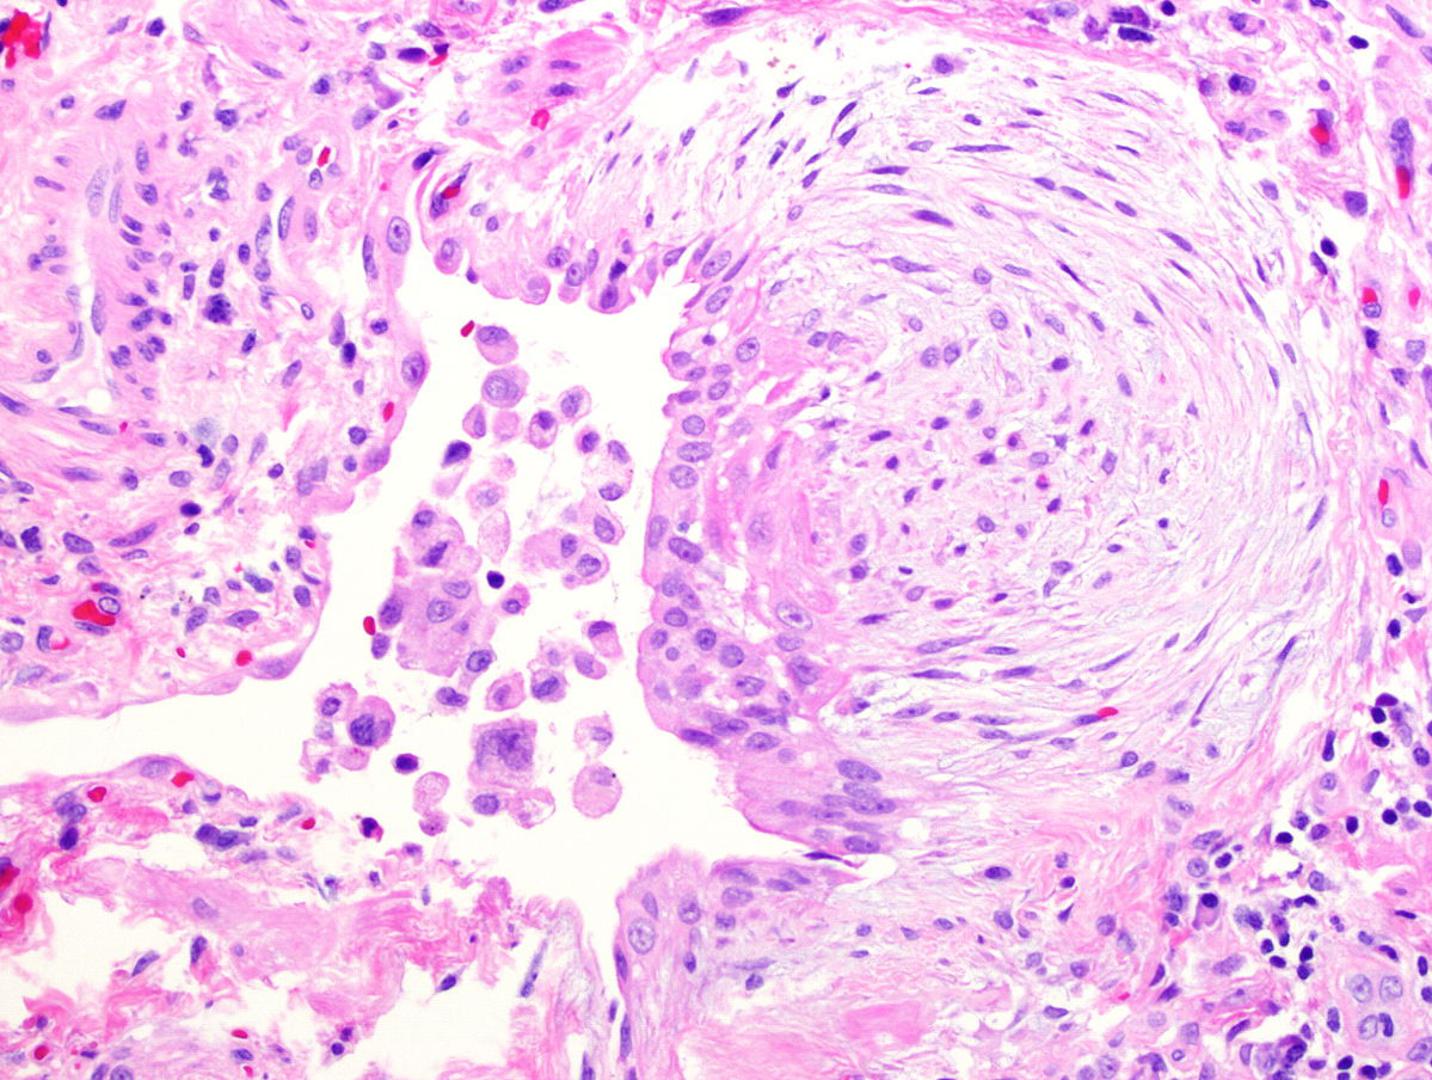

Riječ je o promjeni paradigme, odnosno dosadašnjeg vjerovanja kako takvi virusi jednu vrstu stanica trebaju kako bi ostali u latenciji, dakle neaktivni, a drugu da bi se razmnožavali, ne i jedno i drugo istodobno u istoj stanici. Vjerovalo se da ako je virus prisutan i u latenciji, tada se ne može više u toj stanici razmnožavati. Latencija virusa je situacija kada virus opstaje u organizmu bez da izaziva bolest, ali se može nanovo reaktivirati i ugroziti zdravlje u sklopu stečene imunodeficijencije. To bi bilo, na primjer ako bolesnik biva ozračen zbog leukemije ili prima imunosupresivnu terapiju da se izbjegne odbacivanje presađenog organa. U ovom radu dokazuje se kako takav herpesvirus može ostati neaktivan i razmnožavati se u istoj stanici. Ta stanica bila bi fibroblast, odnosno stanica koja pridonosi stvaranju vezivnog tkiva, vlaknastog materijala koji povezuje tkiva i organe u našem tijelu. Tako je ovo otkriće osobito važno u kontekstu transplantacija jer je kod takvih pacijenata imunitet nakon operacije slab pa pojava citomegalovirusa može biti za njih i fatalna. Ovim se radom dokazalo da fibroblaste taj virus ne koristi samo za replikaciju već i za latenciju. Druga je nova paradigma u ovom radu što virus kontrolira kako će koristiti koju stanicu fibroblasta ali ne samo kroz stanične čimbenike već i kroz interakciju s imunološkim sustavom.

- U članku smo radili na citomegalovirusu (CMV), uzročniku čestih oportunističkih infekcija kod transplantiranih bolesnika, i pripadniku obitelji herpes virusa. Pokazali smo u ciljanim eksperimentima da virusi ove podskupine herpesa održavaju svoju latenciju u stanicama vezivnog tkiva premda se u istim stanicama razmnožavaju. To je novi princip u virologiji, jer herpesi u pravilu koriste jednu vrstu stanica za razmnažanje (npr. stanice epitela usnica) a drugu za latenciju (npr. neuralne stanice trigeminalnog ganglija, čiji zivčani završeci idu do usnica). CMV koristi jedne te iste stanice za obje uloge, a regulacija ovog ciklusa se vrši preko imunih signala, izvijestio je prof. Čičin-Šain.